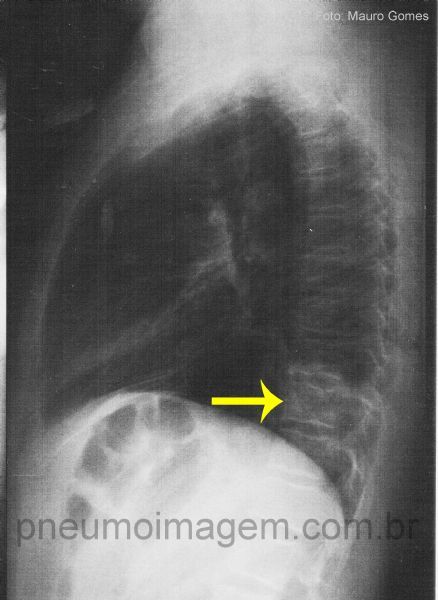

Pneumonia Comunitária em lobo Inferior Esquerdo.

A incidência em perfil permite visualizar a opacidade retrocardíaca, projetando-se sobre a coluna (seta amarela).

Observe a dupla densidade projetando-se sobre a área cardíaca, indicando que deve haver lesão posterior ao coração.